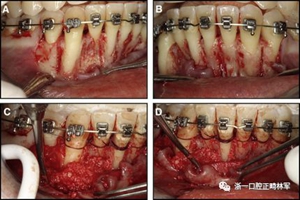

粘合保持器被移除,并放置固定裝置(圖15),僅限于患者要求的下頜弓。在第一階段牙周過程中,將結締組織移植物置于下頜右側中切牙的面?zhèn)取?個月后進行第二階段牙周過程(圖16)。包括有意識的垂直骨質評分以啟動區(qū)域加速現(xiàn)象,以及顯著的面?zhèn)群蜕鄠戎补且约m正骨開窗。隨著時間的推移,全維度弓絲及其表達的牙齒間扭矩差異顯著改善(圖17)。明智的鄰間減少之后,間隙關閉擴大接觸面,消除不美觀的黑三角。在脫粘之前也校正了牙齒排列和牙弓形態(tài)(圖18)。之前和之后的三維圖像(圖19)突出顯示在下頜右側尖牙面?zhèn)缺砻嫔瞎堑脑黾右约扒把姥栏恢玫母纳啤S捎谙骂M切牙的伸長被認為是不嚴謹?shù)?,因此輕度前牙開合沒有被矯正。

圖15.下頜右側中切牙區(qū)域軟組織移植前的初始排齊:A,正面視圖; B,咬合面視圖; C,軟組織移植2周后,初始牙周手術。

圖16.第二階段牙周手術階段,軟組織移植后2個月:A和B,這包括應用骨形態(tài)發(fā)生蛋白,故意骨質損傷引起局部加速現(xiàn)象,以及C和D,應用植骨漿液糾正牙槽骨的開窗(Colin Richman博士提供)。